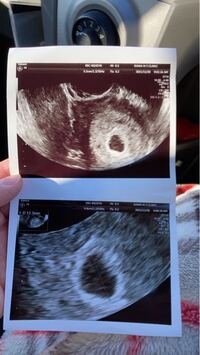

5週と6日 胎嚢は確認できるか 49才 47才で自然妊娠 子沢山

胎芽の大きさ:平均28mm 最小18mm 最大51mm (21名) 心拍確認済みの30名全員が胎嚢・胎芽の大きさを両方とも公表しているわけではないので、あくまで参考値としてみてください。 ちなみにこれを妊娠週数が正確な体外受精の方(14名)に絞ると、胎嚢の 6w2d 胎芽見えない カテゴリ: 不妊治療 鮮血があったり茶オリが続き 頭痛があったり気持ち悪かったり 妊娠が継続してるのか流産してるのか不安な日々を過ごしようやく検診日。 6週めだと心拍確認できる頃ですが胎嚢は大きくなっててもまだ見えない

6週 胎芽 見えない ブログ- 胎嚢は見えるし、卵黄嚢も確認できますが、心拍どころか胎芽も見えません。 でも、胎嚢の大きさは妊娠8週くらいまで育っているから、今回の子は残念ながら成長してない可能性が高いとの事でした。 でも、ちょっと待ってよと。 私の基礎体温表と生理周期を見る限り、妊娠8週に 卵黄嚢、胎芽が見えない 6w2d 上記のとおり、今日で妊娠6週2日です。 胎嚢は2センチでしたが、卵黄嚢と胎芽が全く見えません。 (ちなみに、先週5週3日には胎嚢は1センチでした。 ) 調べたところ、胎芽は6週の終わりに見えたら良いと知りました